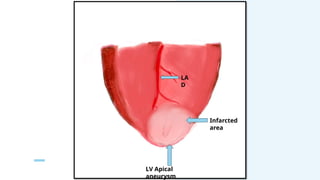

LA

D

LV Apical

aneurysm

Infarcted

area

Longitudinal

ventriculoto

my

septal

tissue

Ventricular

septal defect

with multiple

openings

Dacron patch

placed for

infarct

exclusion

VSR PATCH REPAIR(DAVID’S INFARCT

EXCLUSION TECHNIQUE)+

CABG X2G ( RSVG-LAD and OM)